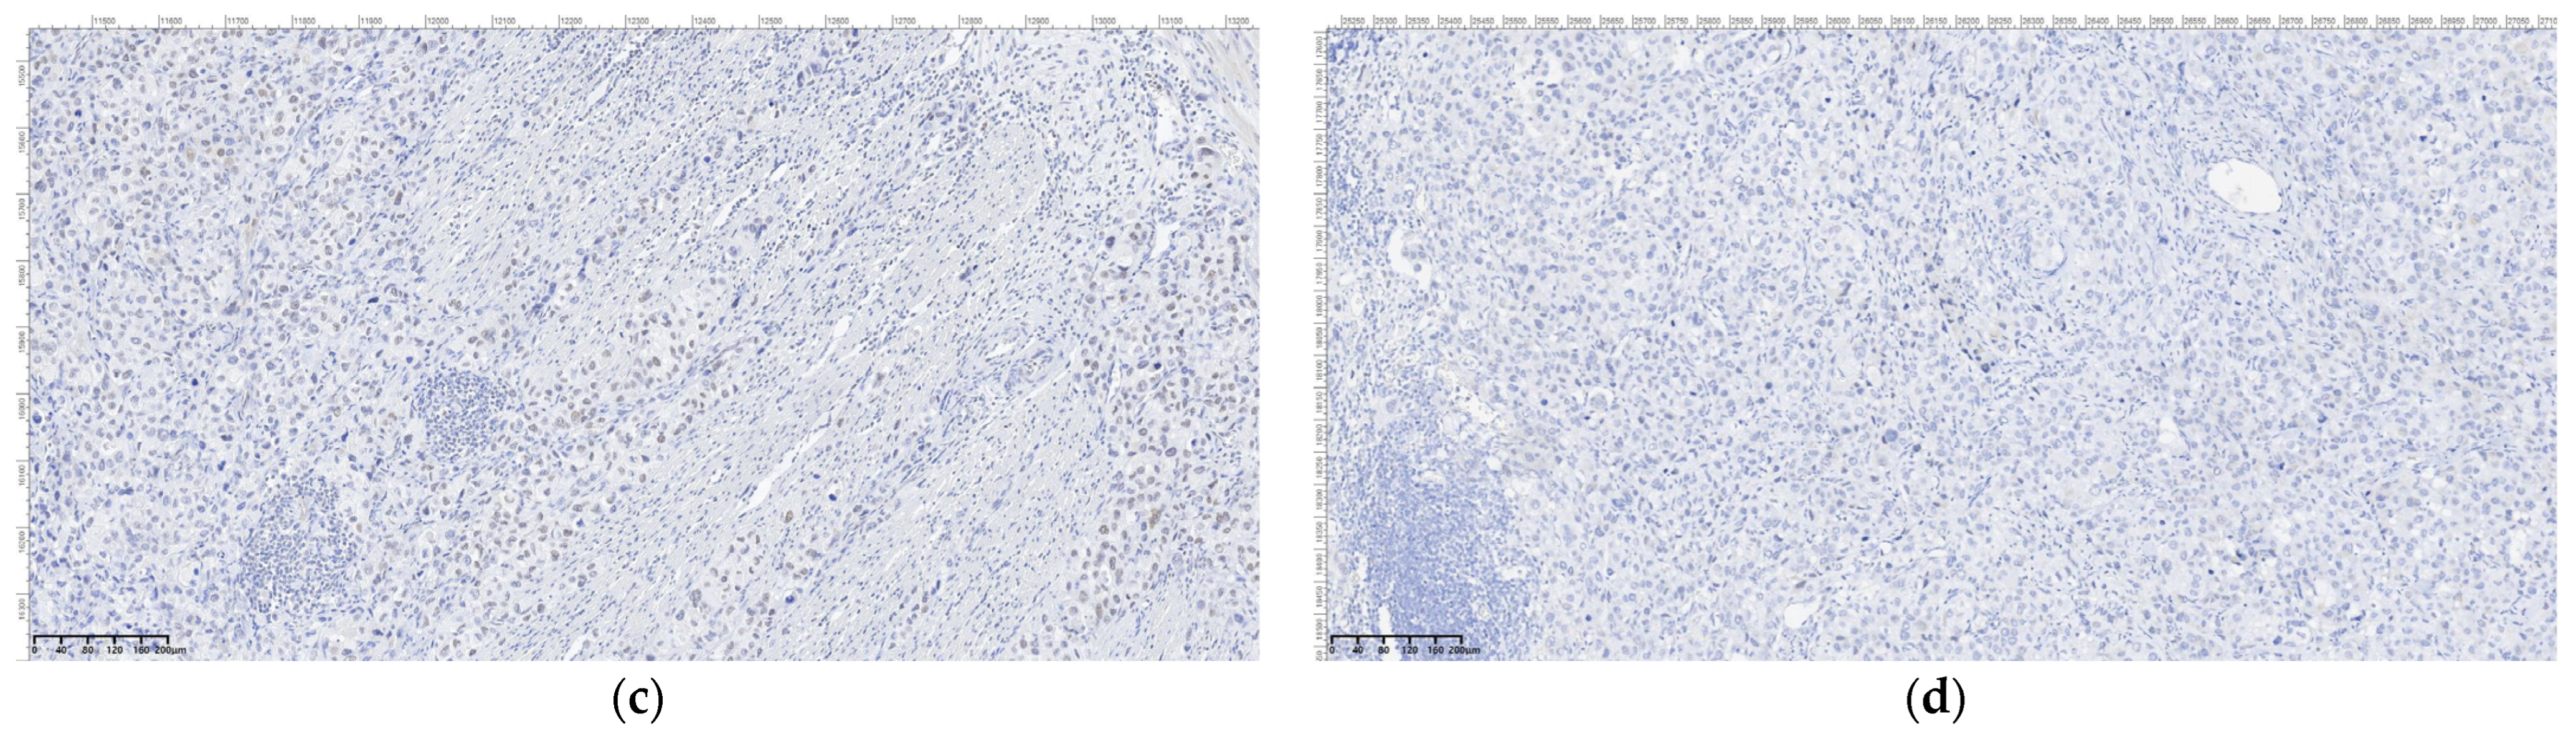

Figure 11.

Sarcomatous carcinoma immunohistochemical diagnosis: (a) SOX 10, OM 200×; (b) PRAME, OM 200×; (c) MelanA, OM 200×; (d) HMB45, OM 200×.

Figure 12.

Sarcomatous carcinoma immunohistochemical diagnosis: (a) DOG1, OM 200×; (b) synaptophysin, OM 200×; (c) SMARCB1; OM 200×; (d) BRAF V600E IHC; OM 200×.